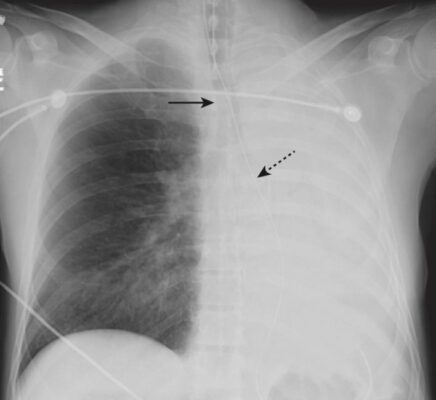

Xẹp phổi toàn bộ (xem Hình 3 và 4)

- Trên phim X quang thẳng:

- Mờ phổi xẹp do mất không khí.

- Nửa cơ hoành ở bên bị xẹp phổi sẽ bị phủ bóng bởi phổi không có thông khí phía trên nó.

- Có sự dịch chuyển của tất cả các cấu trúc di động của lồng ngực về phía bên của phổi xẹp.

- Trên phim chụp X quang nghiêng:

- Nửa cơ hoành ở bên xẹp phổi sẽ được phủ bóng bởi phổi không thông khí bên trên. Nhìn kỹ và bạn sẽ thấy chỉ có một nửa cơ hoành trên phim nghiêng, thay vì hai.